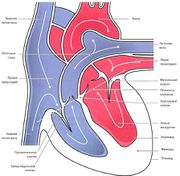

| 01:09, 20 июля 2016 | Mishci sport69.jpg (файл) |  |

46 КБ | Anes | Строение сердца | 1 |